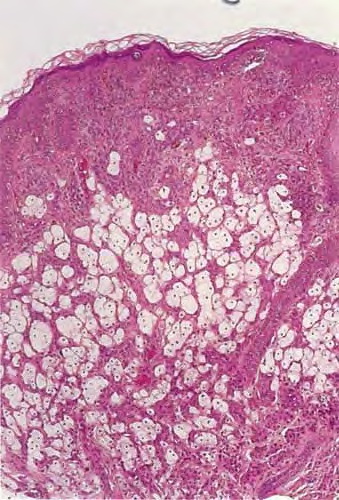

Balloon cells may be seen within the epidermis singly or in groups or may be absent from the epidermis. In the dermis, they lie arranged in lobules of varying size, often with an admixture of ordinary nevus cells and often with transitional forms between the ordinary and ballooned nevus cells . The balloon cells may be multinucleated and are considerably larger than ordinary nevus cells. Their nuclei are small, round, and usually centrally placed. Their cytoplasm appears empty, finely granular, or vacuolated, often with a few small melanin granules. There may be melanophages that are solidly packed with pigment. Stains for lipids, glycogen, and acid or neutral mucopolysaccharides are negative in the balloon cells. Electron microscopic examination reveals in balloon cells numerous large vacuoles formed by enlargement and coalescence of degenerating melanosomes . Balloon cell nevus is differentiated from balloon cell melanoma by the usual criteria. The large adipocytes present in some intradermal nevi as a result of fatty infiltration or stromal metaplasia differ from balloon cells by routine histology by having a flattened nucleus located at the periphery of the cell. In the differentiation from clear cell hidradenoma and other clear cell tumors, the absence of periodic acid-Schiff-positive glycogen and keratin in balloon cell nevus might be helpful; balloon nevus cells also stain for S100 protein, and although eccrine neoplasms (and adipocytes) may also express this marker, they will also usually be positive for Melan-AIMART-1 and negative for keratin markers.